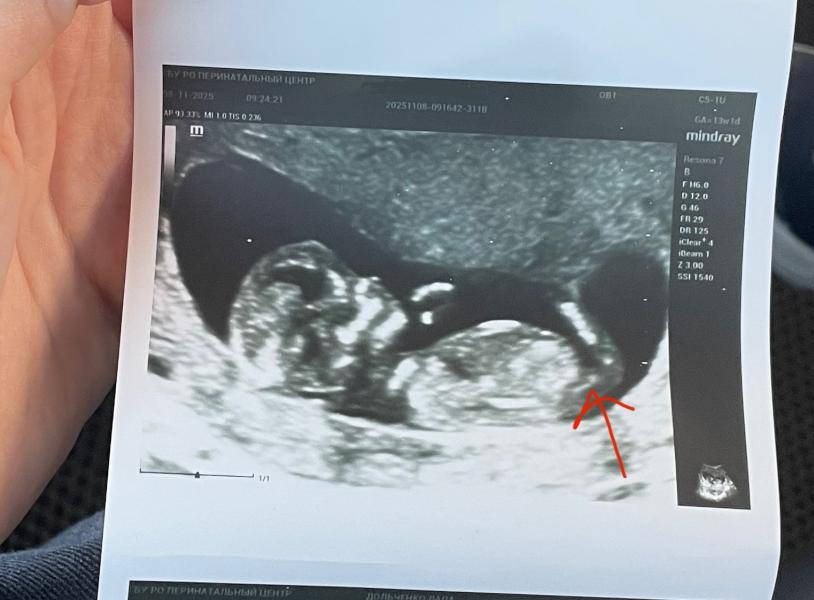

Не могу понять, это половой бугорок или бедренная кость?😅🙈

@dianka_gam, так он же и у девочек есть, просто под разным углом расположен🤔

@ladylada_ вот именно, а у вас этого вверх стоящего бугорка нет 😂😂😂

@linka-plyt, мне-то предположили, я просто пытаюсь понять по каким признакам 😅 с сыном не ошиблись на том же сроке))

@ladylada_, ну если сбоку то обычно смотрят если половой бугорок лежит то девочка, если вверх поднят то мальчик)

Да кость это) бугорки по другому выглядят. Говорю как мама двух пацанов 😂

Я вот не запомнила какой бугорок у мальчиков😅 Но тоже больше склоняюсь, что это кость